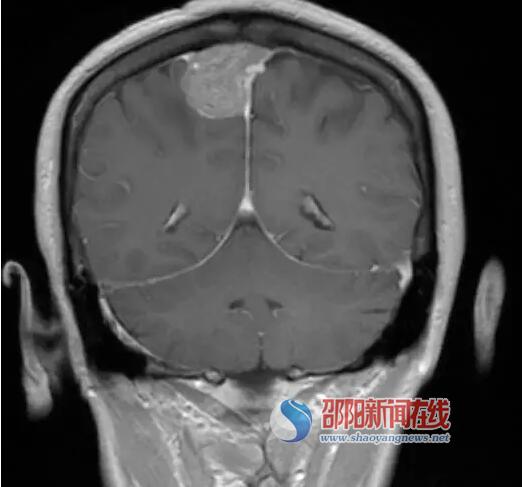

为求进一步治疗,李阿姨来邵阳市中心医院神经外科就诊,入院后积极完善相关辅助检查。神经外科钟志坚、孙海鹰教授根据患者CT及MRI检查提示右侧顶叶占位性病变,考虑脑膜瘤可能性大,目前已经出现左侧肢体麻木、不全瘫痪,肢体肌力III级(正常成人肢体肌力V级),如果不早日手术,随着肿瘤持续增大,症状会继续加重,会出现左侧肢体完全性瘫痪。但因为肿瘤位于运动、感觉功能区,且位于大血管矢状窦区,手术风险高、难度大,特别如果术中出现静脉窦的破裂,可在短时间造成大量出血,如果处理不当,有可能出现失血性休克、空气栓塞或颅内静脉回流障碍,引发致命性的脑肿胀;这也是常见的术中紧急情况。若术者缺乏相关经验,有可能引发严重的不可逆后果,如何最大限度地精准切除肿瘤的同时减少并发症是术者需要慎重思考的问题。

(术前头颅MRI)